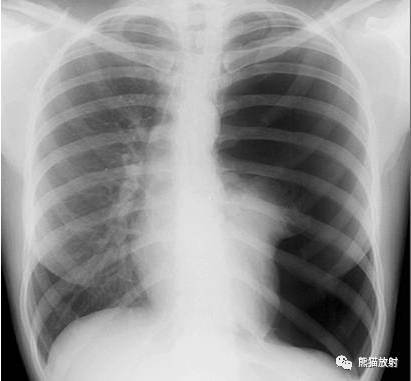

左侧气胸(肺被压缩约95%):

左侧胸腔透亮度广泛增高 , 其内未见纹理走行 , 左肺明显受压缩小 , 紧贴于左下肺门处 , 纵隔略向对侧移位 。